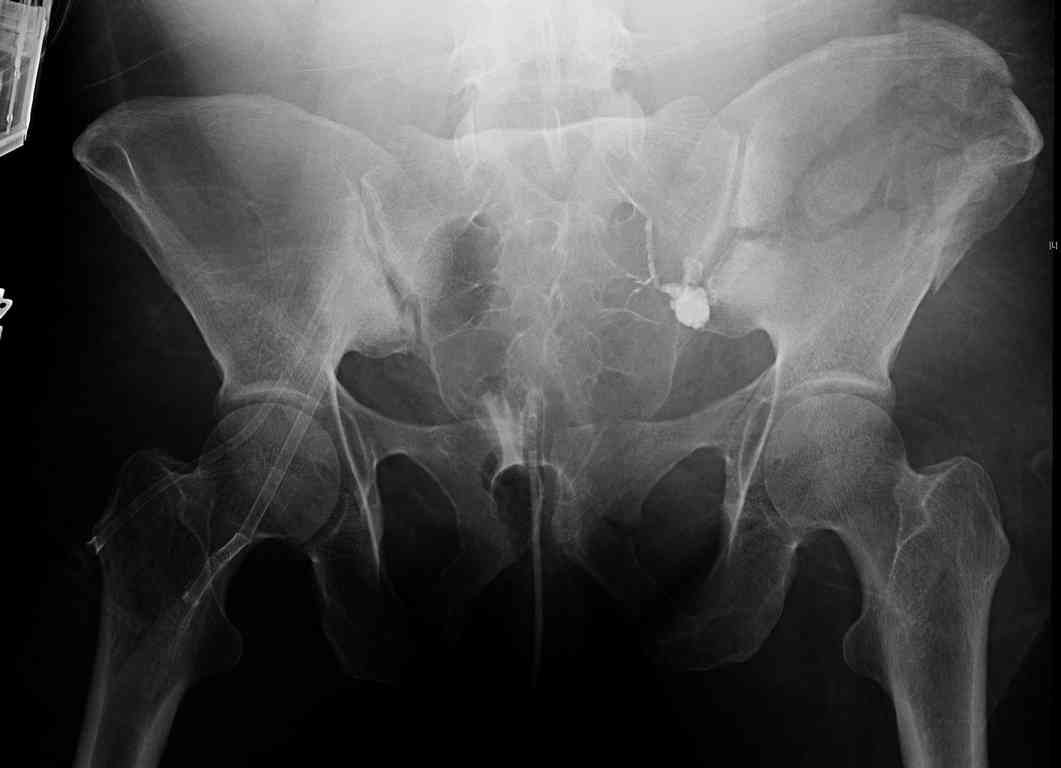

[Ortho] comminuted crescent fx

Any advice would be appreciated:

40 ish female ejected from car. Unstable, DPL negative, went to angio and had her pelvic bleeds embolized after many units of blood. GCS 6, floating elbow, clavicle, bothbones, etc.

My standard approach to  this pelvis would be posterior, reduce/lag/plate  thecrest, reduce/plate the caudal extent on the posterior crest and 1-2 lags back to front. In this case, the crest comminution seems to make plating all

the way to the ASIS useless, as the plate would be on free floating fragments. Would plating the posterior extent of the fracture to secure the

reduction at the SI joint and 2 screws back to front be sufficient fixation? Would anyone do a perc reduction and perc back to front screws, and would that be sufficient if the SI joint could be reduced (although I don't see how this could be accurately reduced closed). Would an ilioninguinal with a pelvic brim plate and posterior column screws be a better approach, although reducing the SI would be more indirect and less accurate?